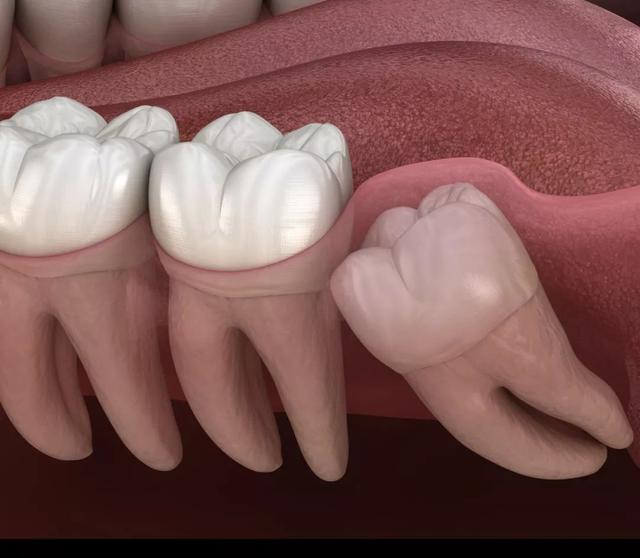

反之,如果是反复疼痛的,出现阻生情况比如前倾、后倾、水平、倒置等现象的,这样的智齿最好还是拔掉,因为它是没法长正的。而且,可能今年还只是智齿发炎,过几年,它前面的邻牙很有可能被侵及,再拔牙就得拔一颗送一颗啦!

通常智齿萌发的空间不足,而会倒在第二大臼齿上,因而造成第二大臼齿清洁不易,甚至是牙齿部分吸收的现象,造成患者不舒适或牙疼。

5、阻生齿

通常这是最讨厌的一种,牙医会觉得很难搞定,但患有者却不一定有感觉,一般需要拍片才能看得出来了,所以患有者容易忽略。这一种类型的牙齿,通常埋在齿槽骨的里面,如果会痛,或是诊断会有病灶发生的时候,就需要拔除了。